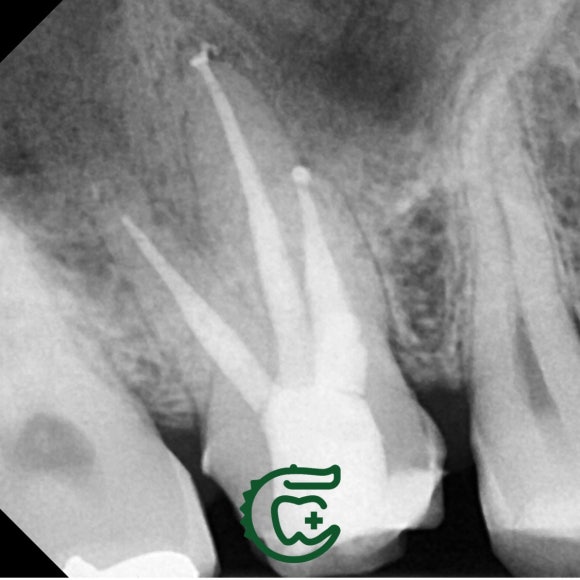

미세 현미경 하에서 이전 치료들에서 놓친

신경관을 찾아 청소해주니,

그 즉시 증상도 사라지고

상악동 내의 염증 소견도 사라졌네요.

깔끔하게 신경치료를 마무리 해드렸습니다.